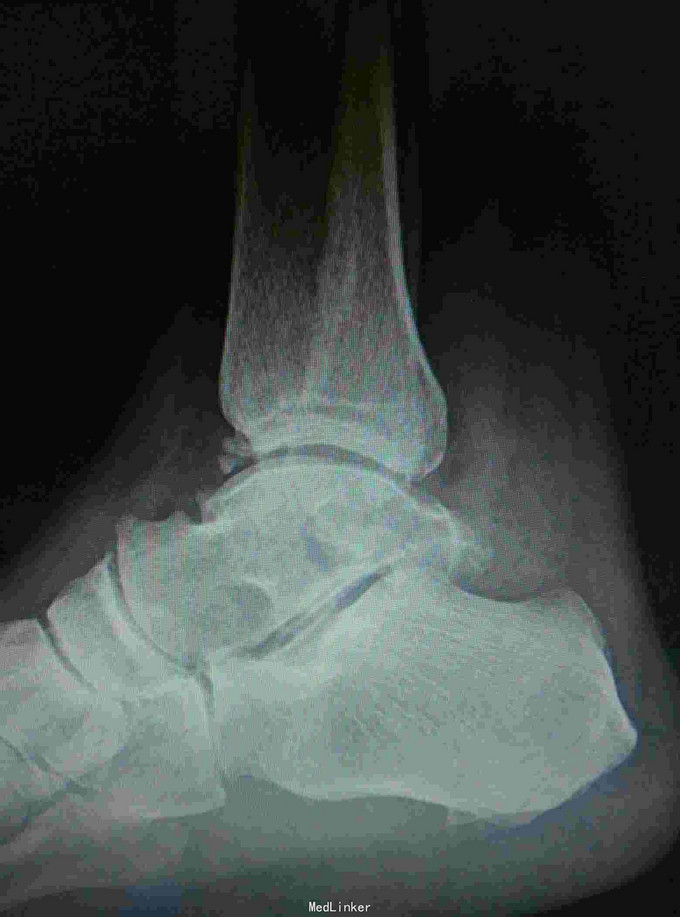

患者,男,45岁,车祸伤致右踝部肿痛,活动受限2小时入院

入院查体见局部肿胀,予完善影像学检查,

诊断是右距骨粉碎性骨折。给予行内踝截骨显露骨折端进行复位,采用Herbert钉进行固定。

术后复查X线片提示骨折端完全复位,内固定固定在位良好。 讨论:距骨骨折的主要并发症是坏死,骨不愈合等,但近年来随着对其认识的不断明确,治疗比较规范,积极的进行切开复位,并行坚强固定,近年的研究报告提示距骨的坏死率是不断在下降的,当然前提是进行有效复位并坚强固定。